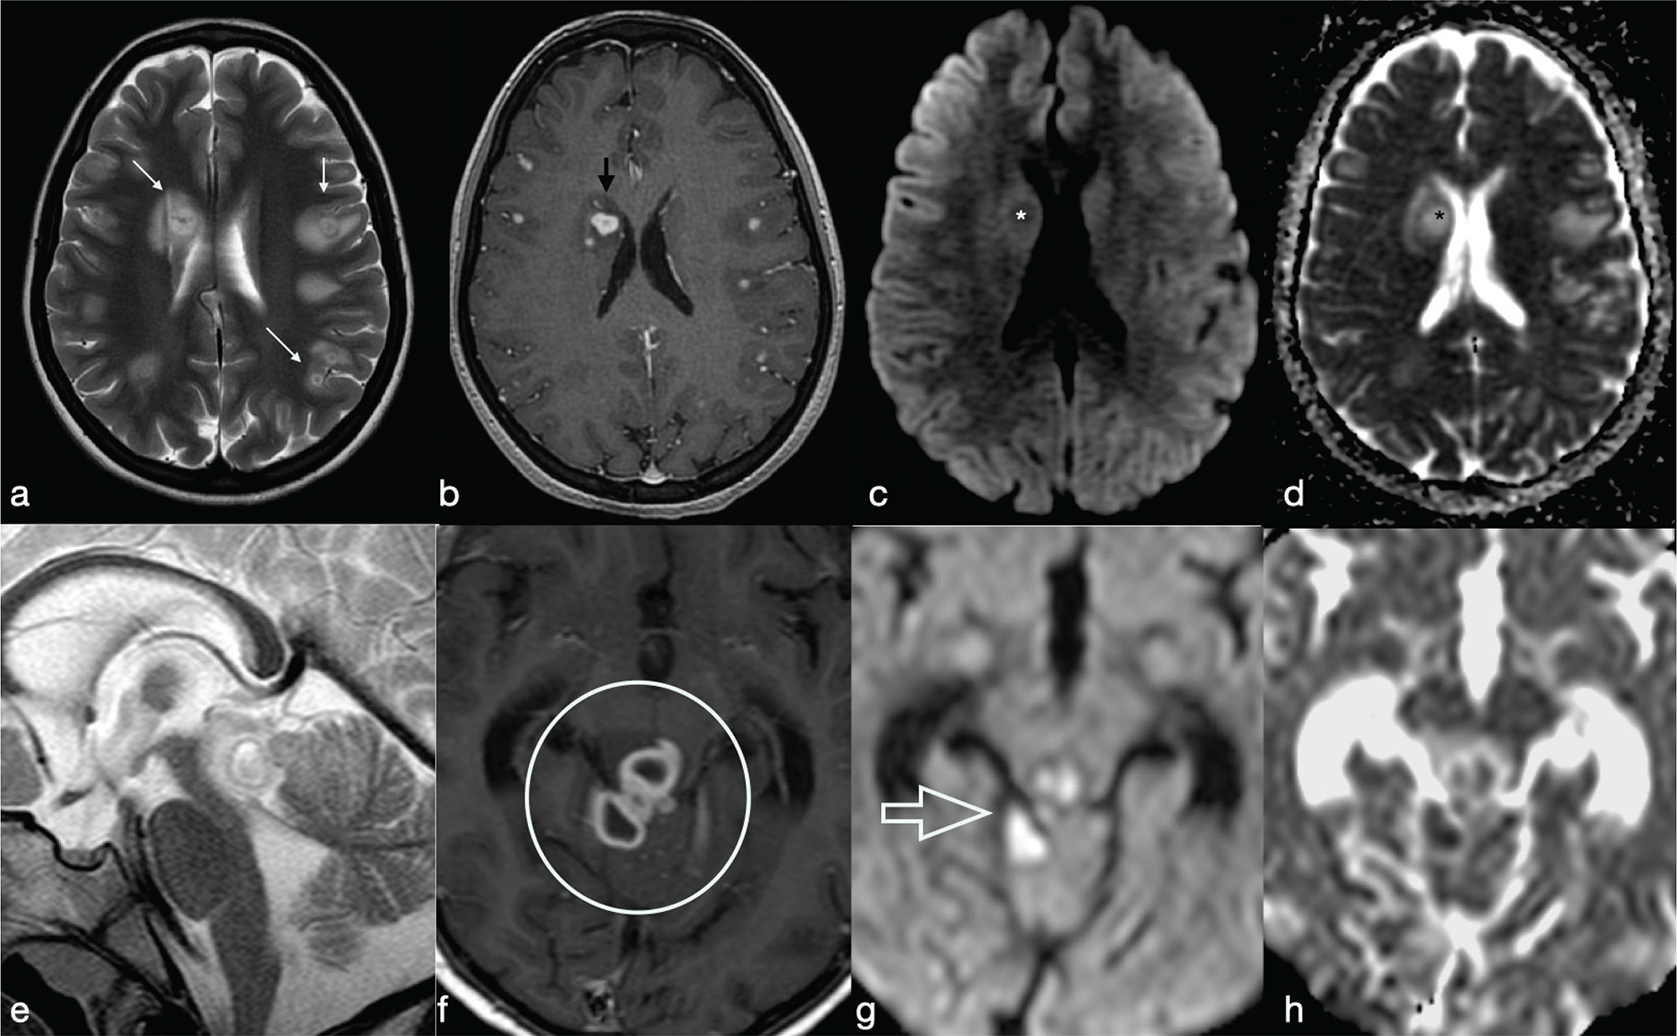

FIG 14. Tuberculoma (a–d) and Tubercular Abscess (e-h). Multiple tuberculomas in both cerebral hemispheres with an hypointense central dot (white arrows in a) within an hyperintense core on T2w are demonstrated. Nodular enhancement on T1+Gd is shown on smaller lesions while the larger one (black arrow in b) shows a thick ring delimitating a cystic core. On DWI and ADC map there is no restricted diffusion (asterisks in c-d). On the contrary, tubercular abscesses located in the quadrigeminal plate show a bright core on T2w, thick peripheral enhancement on T1+Gd (open circle in f) and restricted diffusion on DWI (g) and ADC maps (h).